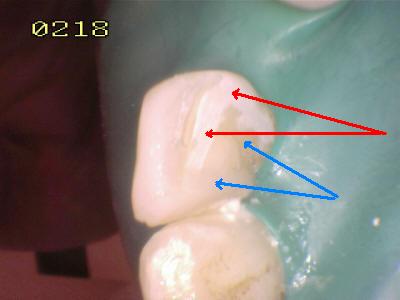

Flechas rojas: Esmalte grabado   Flechas azul resina compuesta